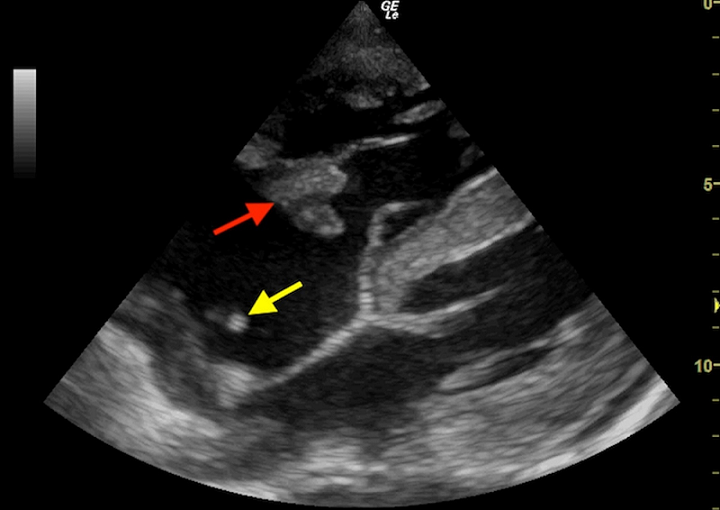

A 32-year-old man with end-stage kidney disease secondary to chronic glomerulonephritis, on maintenance haemodialysis via a right internal jugular central venous catheter for three months, presented with a one-day history of worsening dyspnoea, fever, chills, non-productive cough, and central chest pain. On examination, he was febrile with a temperature of 38.6°C, tachycardic at 126 beats per minute and blood pressure was 150/98 mmHg. His oxygen saturation was 88% on room air which improved to 96% with supplemental oxygen. Chest examination findings were consistent with bilateral pleural effusions. Jugular venous pressure was not elevated and no murmurs were heard. Point-of-care ultrasound demonstrated a large echogenic mass attached to the anterior leaflet of the tricuspid valve consistent with vegetation (red arrow), with the tip of the central venous catheter visualized within the right atrium (yellow arrow). Mild pericardial effusion and bilateral pleural effusions were also noted. Laboratory evaluation revealed marked leukocytosis with a white blood cell count of 28.6 x 109/L and neutrophil predominance, with severe anaemia (haemoglobin 7.2 g/dL). Blood cultures were obtained for suspected infective endocarditis following the ultrasound findings and empiric intravenous antibiotic therapy was initiated promptly. However, the patient deteriorated rapidly and died the following day. This image highlights the importance of maintaining a high index of suspicion for catheter-related infective endocarditis in patients undergoing haemodialysis. It demonstrates the critical role of point-of-care ultrasound in the early detection of life-threatening cardiac complications associated with central venous catheters.